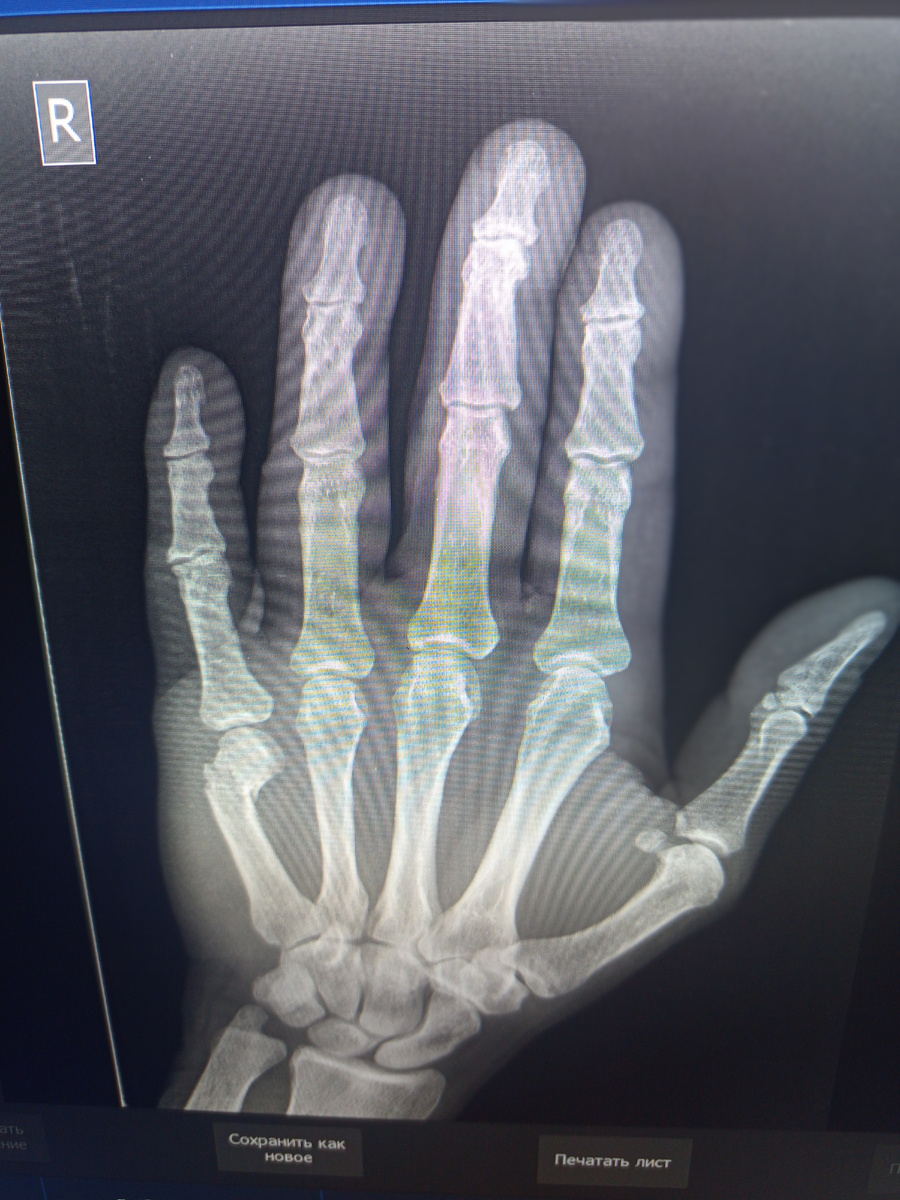

Пришел мужчина на снимок кисти, Какая-то балка на руку упала.

Да , есть перелом в типичном месте.Рука сильно опухла.

Через некоторое время приходит на контрольный снимок, с врачом, которому не терпится глянуть.

Проявляем снимок. Конечно , видно , что не попал.

–Да , уж, –досадливо говорит врач.

–Да вообще! Не смог подобраться к костям , еще и полная рука! Не прощупал!Вот и что мне с ним делать?

–У вас есть еще шансы , в головку же попали, ну чуть лучше репонируите,ближе кости надо сдвинуть.

Поверьте , мы опытные лаборанты , понимающие во многом том , что делаем. Давно знаем , что чем полнее рука , тем сложнее выполнить идеальную репозицию косточек.

Привел второй раз.Попал.

–Ну вот видите!Молодец!

–Да мне все равно кажется , что не идеально сопоставил.

–Доктор, лучшее–враг хорошего, сейчас подправите и идеально!

–Скажете тоже, –смущается молодой врач, подающий надежды .